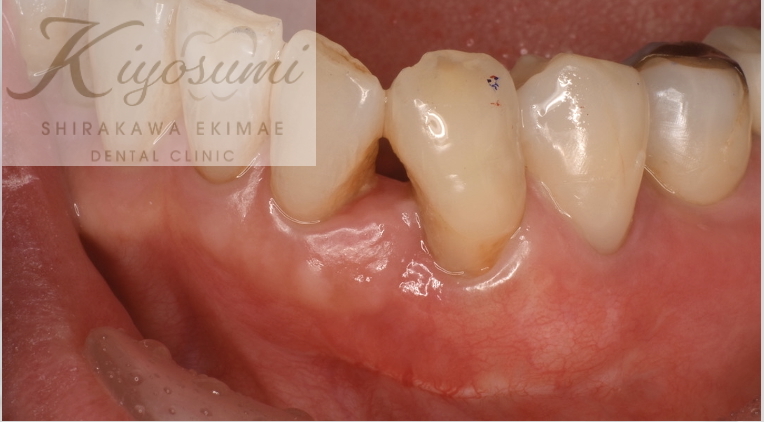

| 主訴 | 笑うと歯茎が目立ち、歯の長さが短い気がする。 |

| 治療内容 | デジタルワックスアップ、CTでシミュレーション後、歯冠長延長術を実施しました。 |

| 想定されたリスク | ※一度治療しても、長期経過で後戻りが起こるリスクがありました。 ※手術後、知覚過敏、歯肉退縮、後戻りが起こるリスクがありました。 |

お口とスマイル時のお顔のスキャンデータ、CTデータを重ね合わせて手術のシミュレーションを行い、歯の長さを出すために歯茎と骨を調整する歯冠長延長術を行いました。